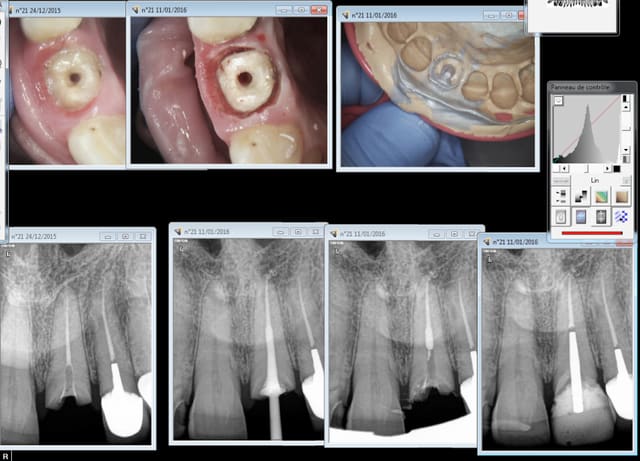

Bonjour, je suis à la recherche de forets pour la réalisation de logements de tenon qu'utilisez-vous? et pourquoi avez vous choisi tel ou tel?

Je précise ma demande je voulais savoir quelle marque prenez vous ? Et pourquoi cette marque plutôt qu'une autre.

largo pour desobturer (2 puis 3). Les gates marche bien pour aller un peu plus loin mais passage d'un largo derriere obligatoire

J'utilisais le systeme Apol, tres efficace, mais trop efficace^^. Tu peux vite perforer si tu fais pas gaffe

Depuis j'utilise le systeme dentoclic, ca fait le taff. Mais les pivomatic et les conneries du genre, ca doit revenir aux memes

Gates 2/ largo 2/ gates 3 / largo 3 / pivomatic blanc, qqf pivomatic jaune, et tenons itou.

Moi, j'utilise les torpans K Reamer longueur 18mm N° 20 à 55 puis forets cylindro coniques Dentoclic jaunes. Le pb c'est qu'on ne trouve plus les K Reamer en France. Dentsply ne les vend qu'à l'étranger (Italie, USA).

J'ai abandonné les Pivomatics pour le système Exotec.

3 diamètres (3 couleurs), même forets pour les tenons fibrés, les tenons à empreinte (2 longueurs et clavette) et tenons à provisoire (3 longueurs).

Forets largo 1/2/3/4 (en fonction du canal ) pour la descente puis forets dentoclic (pas cher) pour l'élargissement modéré.

Dento clic ou pivomatic rouge. Foret largo 3 d'abord ( passé meme avant lors de l'endo) . Stop à 10 mm sur les forets. Tu peux meme le faire pendant la séance de l'endo si tu possèdes un heater plugger mais un machtou bleu chauffé ca marche aussi